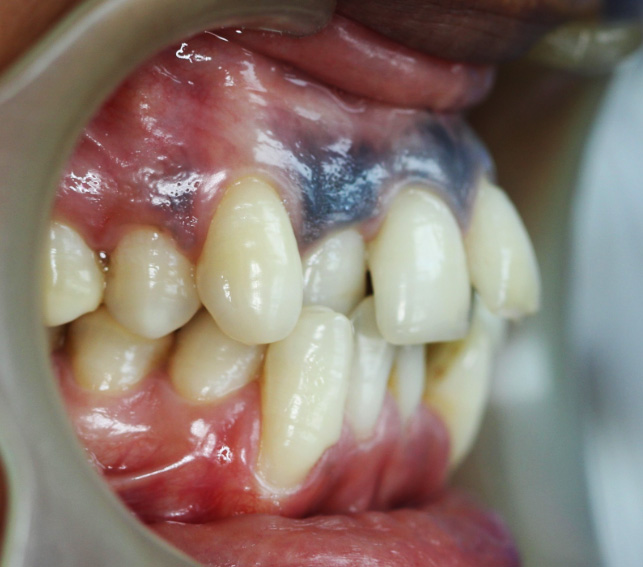

Intraoral Images: — (Before-treatment images)

The patient was diagnosed with Angle’s Class I malocclusion, along with crowded teeth and a crossbite. These conditions caused improper alignment of the teeth and an uneven bite.